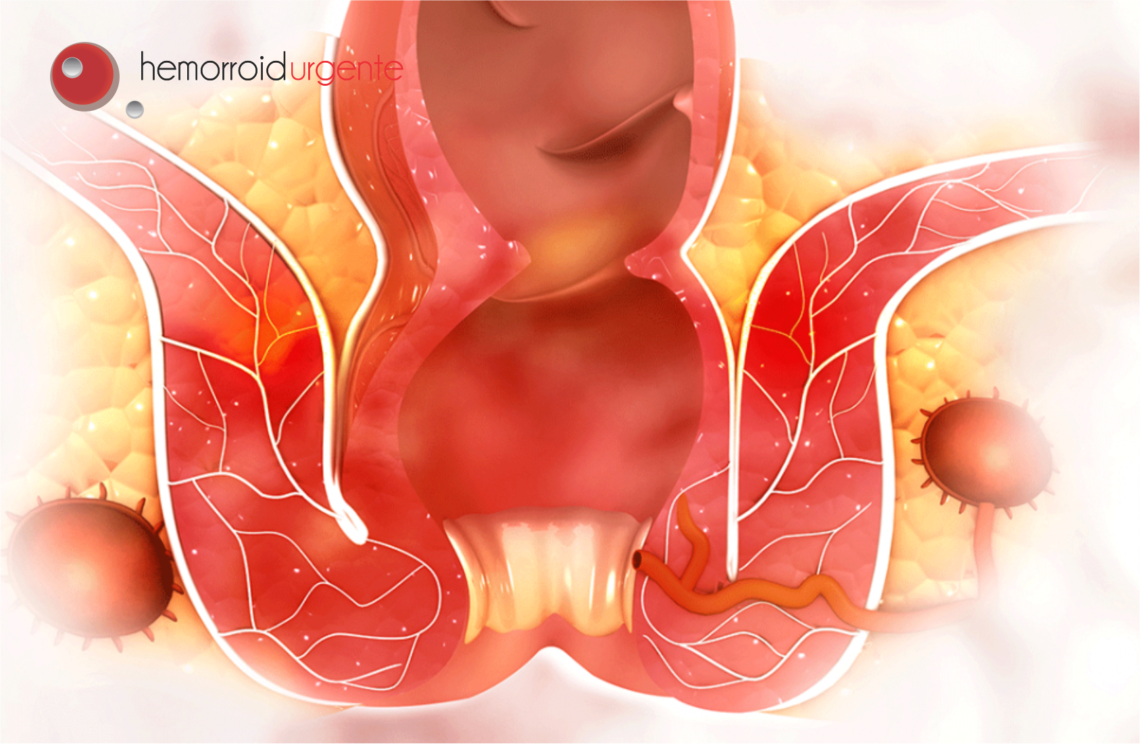

A hemorroida acontece quando as veias do ânus ficam inchadas e estufam a pele da região. Essas veias inchadas podem sair para fora do ânus ao evacuar, causam coceira, dor, ardência, latejamento e geram uma secreção que dificulta a higiene no local. Para cada caso, há um tratamento específico, por isso é tão importante procurar um médico da área de coloproctologia. Mas, de um modo geral, todos podem tomar algumas atitudes e cuidados que vão ajudar a amenizar essa crise.